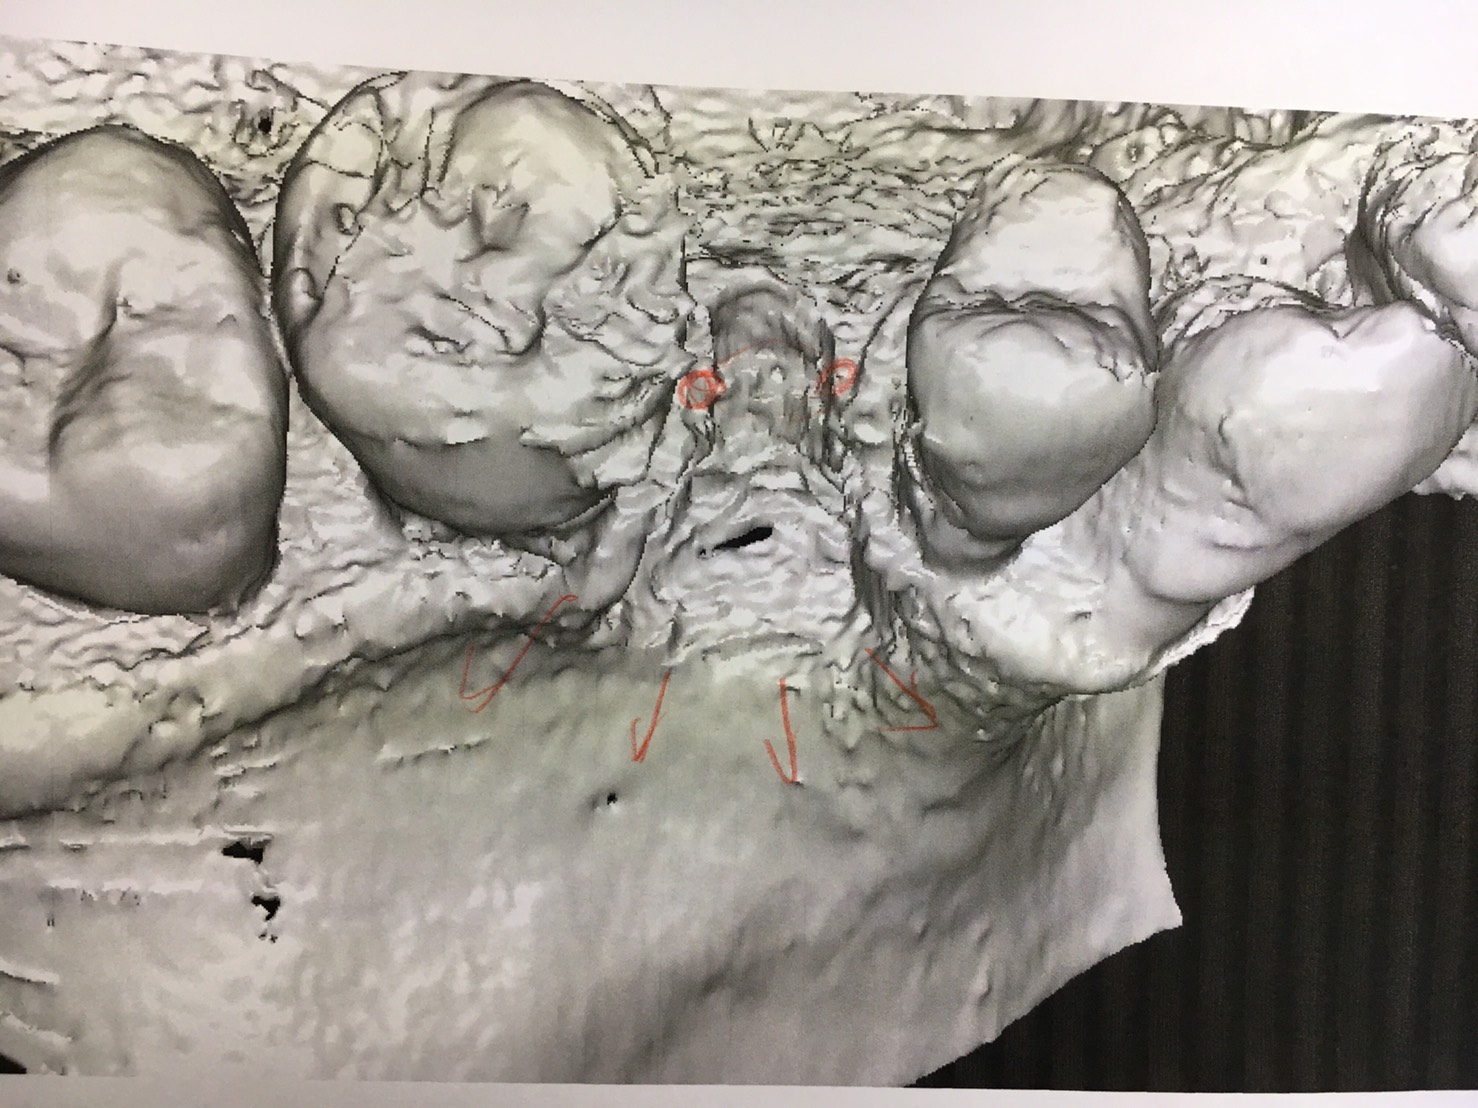

本日は浅草橋分院にて須田理事長のインプラントオペ 部位は左上5番ソケットリフト 残存骨高さは2ミリから5ミリのスロープ形態の難易度高いオペです スリットやらベント等の穴を始めに作りアプローチ窩からも膜を剥離し5ミリ位の挙上が得られバッチリですね! 術前の3D画像からも、難しさが分かります